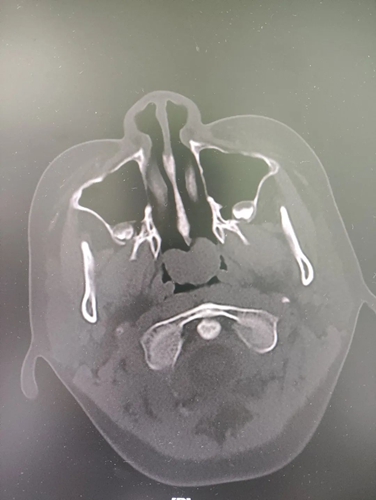

耳鼻喉科接診醫(yī)生查體發(fā)現(xiàn),可可的鼻塞不伴隨打噴嚏和流鼻涕。進(jìn)一步詳細(xì)檢查,結(jié)果顯示,可可的左側(cè)鼻腔后端有一處直徑近2厘米的腫物。腫物不僅堵塞了后鼻孔及鼻咽部,還阻礙了鼻竇的引流,引起了鼻竇炎。